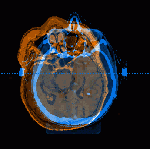

With any type of cancer, radiation therapy delivered to cancer cells damages and kills them. But, radiation also reaches the surrounding normal tissue and can damage or destroy it as well.

These side effects may include swallowing difficulty, voice changes, ulceration in throat, pain, and long term scarring. Precision in radiation therapy is very important to help reduce these side effects.

- Intensity modulated radiation therapy (IMRT)